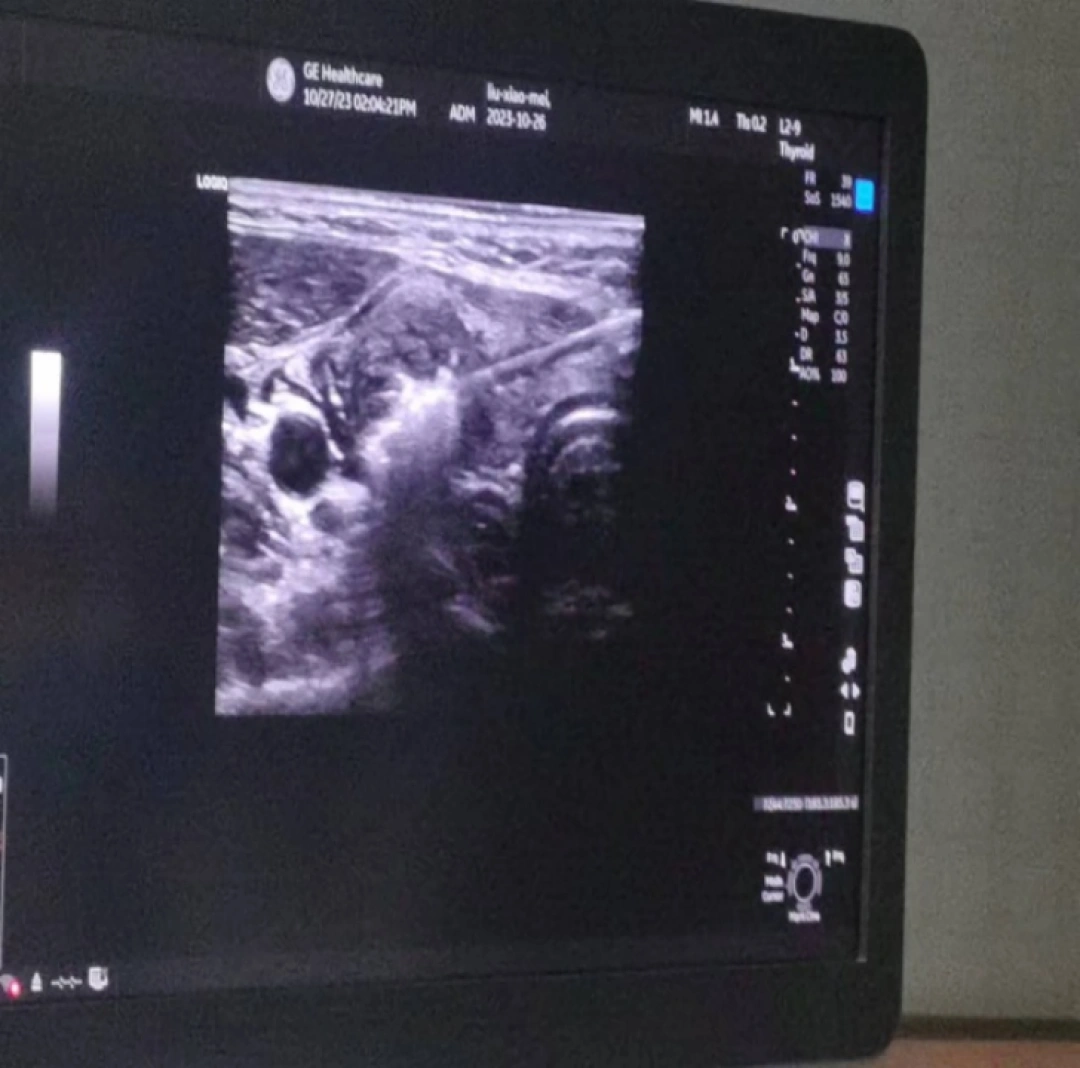

当天,手术在超声介入室进行。在局麻下借助彩超设备对病灶和治疗针具的精确显示和引导,将微波消融针穿刺到甲状腺病灶内,通过微波产生的高温,引起病灶组织发生局部凝固性坏死,整个手术过程耗时不到30分钟,术后超声造影进一步证实甲状腺结节血供消失,瘤体完全灭活。

△手术前和手术中超声影像对比。